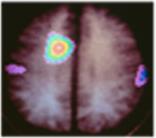

These images (courtesy of Michael E. Phelps from Science 211:445, 1981) were produced in a PET scanner. The dark areas are regions of high metabolic activity. Note how the metabolism of the occipital lobes (arrows) increases when visual stimuli are received.

Similarly, sounds increase the rate of deoxyglucose uptake in the speech areas of the temporal lobe.

This image (courtesy of Gary H. Duncan from Talbot, J. D., et. al., Science 251: 1355, 1991) shows activation of the cerebral cortex by a hot probe (which the subjects describe as painful) applied to the forearm (which forearm?).